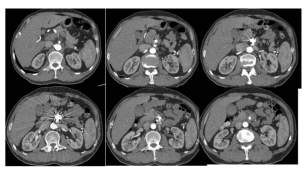

经过手术,老徐转危为安,他的腹痛明显缓解,也开始正常进食。术后一周,他的CT血管造影显示:支架通畅,假腔无显影,无并发症。老徐终于笑着出院了。

术后一周CTA